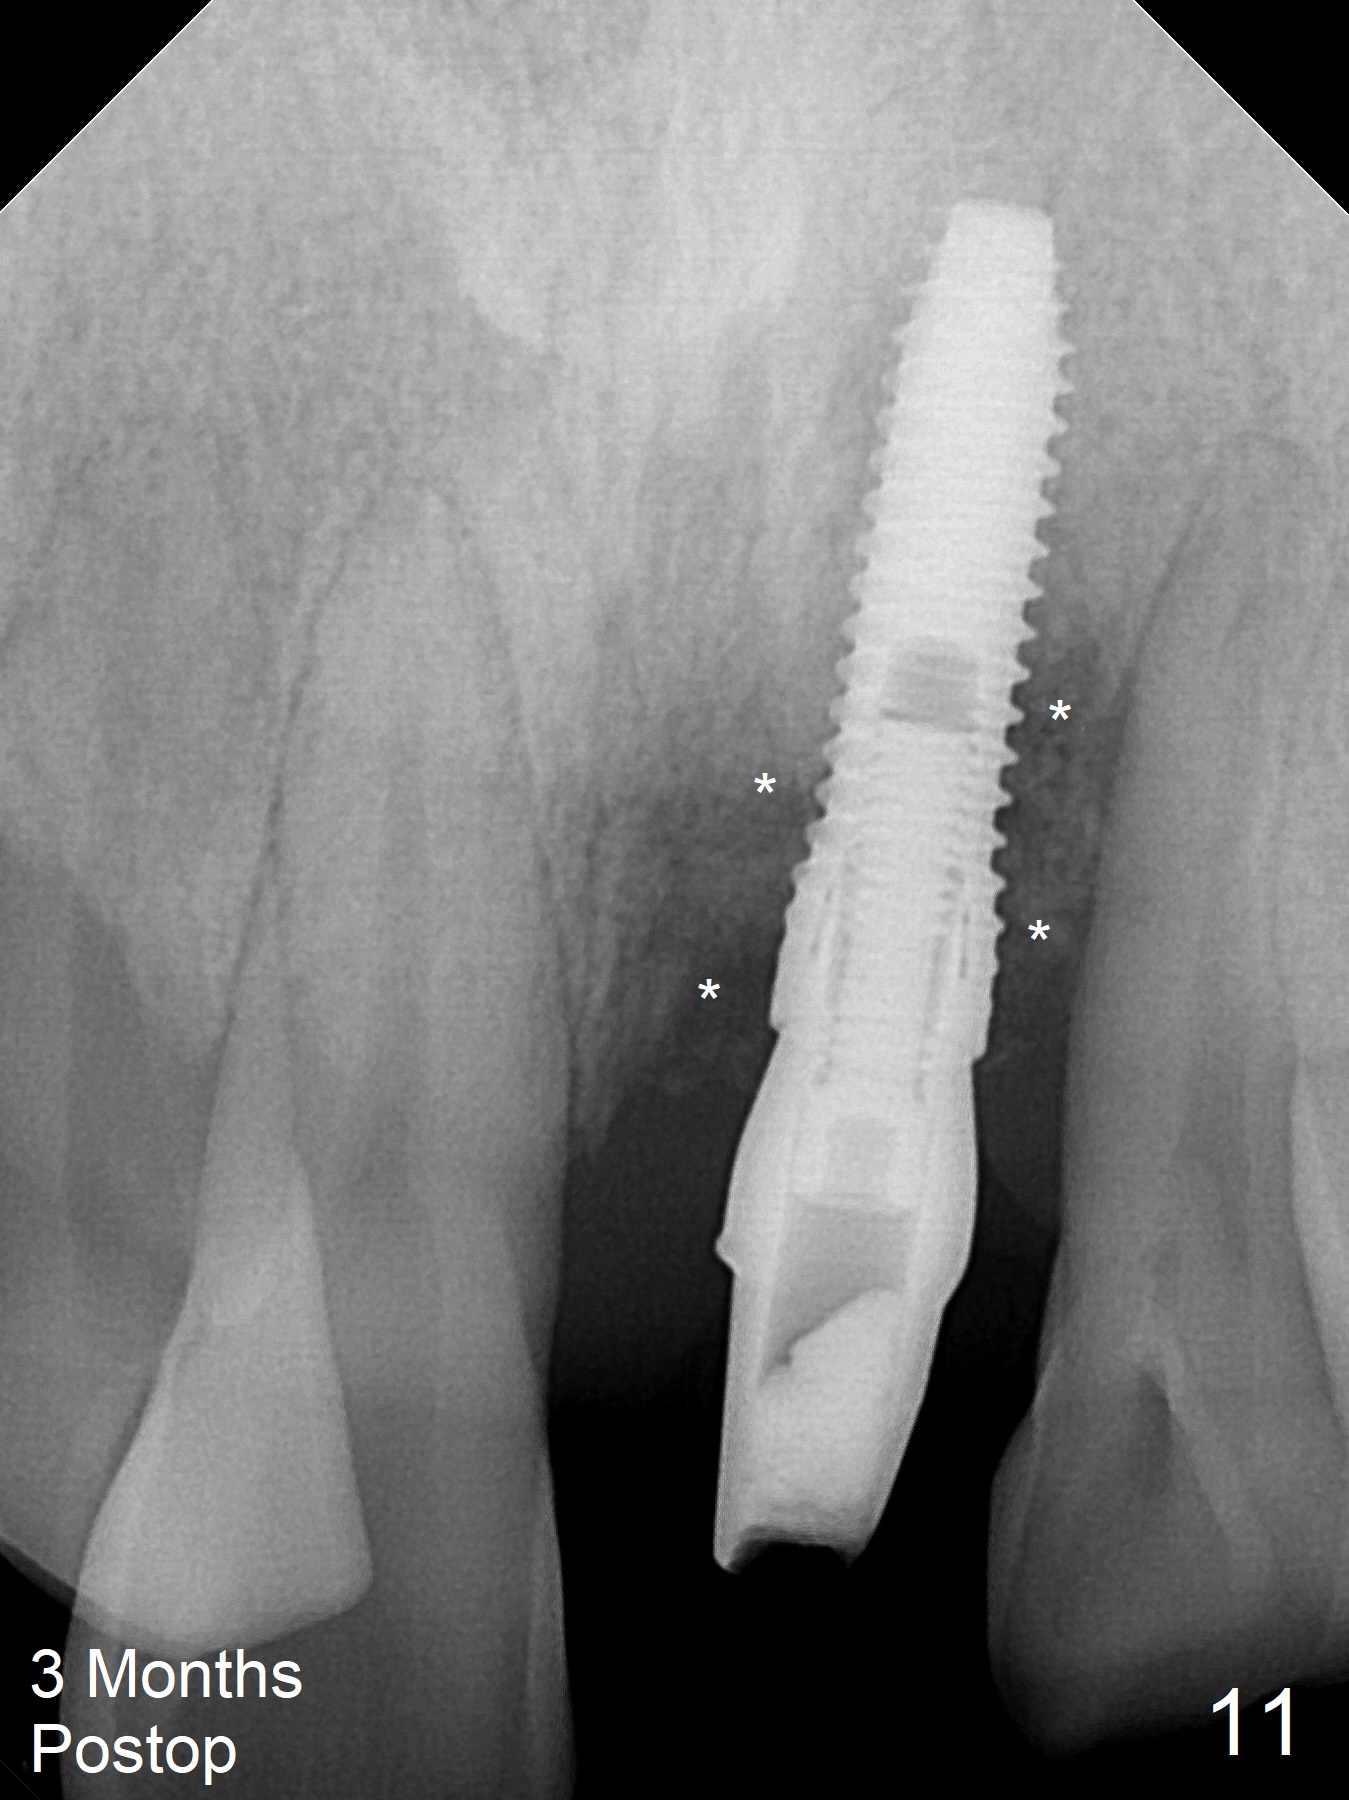

Immediately preop PA confirms loss of the buccal plate at #9 (Fig.1 *). In contrast the palatal crest is ~ 4 mm subgingival (WNL) after extraction. When initial osteotomy reaches 18 mm, there is moderate hemorrhage, probably due to close to the nasal floor (Fig.2 red dashed line). Following sequential osteotomy, a 3.8x15 mm dummy implant is placed partially (Fig.3 (pink: apical osteotomy)). After placement of an implant with the same dimension as the dummy's (Fig.4), PRF is laid against the inner surface of the buccal defect and allograft (Fig.5 *) is packed mainly in the buccal gap before and after insertion of a 4.5x5(4) mm abutment. The patient is satisfied with the immediate provisional (Fig.6: 1 week postop). The buccal margin of the provisional is shortened with exposure of bone graft to facilitate gingival downgrowth (Fig.6: 1 month postop). The buccal plate seems to collapse nearly 2 months postop (Fig.8 *), probably due to loss of the bone graft. The abutment is exposed buccally (Fig.9). The margin of the abutment is reprep and the provisional is relined so that the margin of the provisional is palatal to the buccal gingival margin. In 2-3 weeks, a temporary abutment will be used to bulk the buccal gingiva. The gingiva seems to have downgrown; the buccal plate collapse appears normal nearly 3 months postop (Fig.10). The patient is more concerned about cross bite at #7. A temporary abutment is not used. The bone graft remains in place 3.5 and 4.5 months postop (Fig.11,12 *). Between 3 and 4 months postop, the mesial surface of the abutment has been trimmed (Fig.12 >). Since the mesial surface of the tooth #10 will be reduced (white curved line) to correct the upper dental midline, an angled abutment (red line) seems to be necessary to shift the provisional distal.